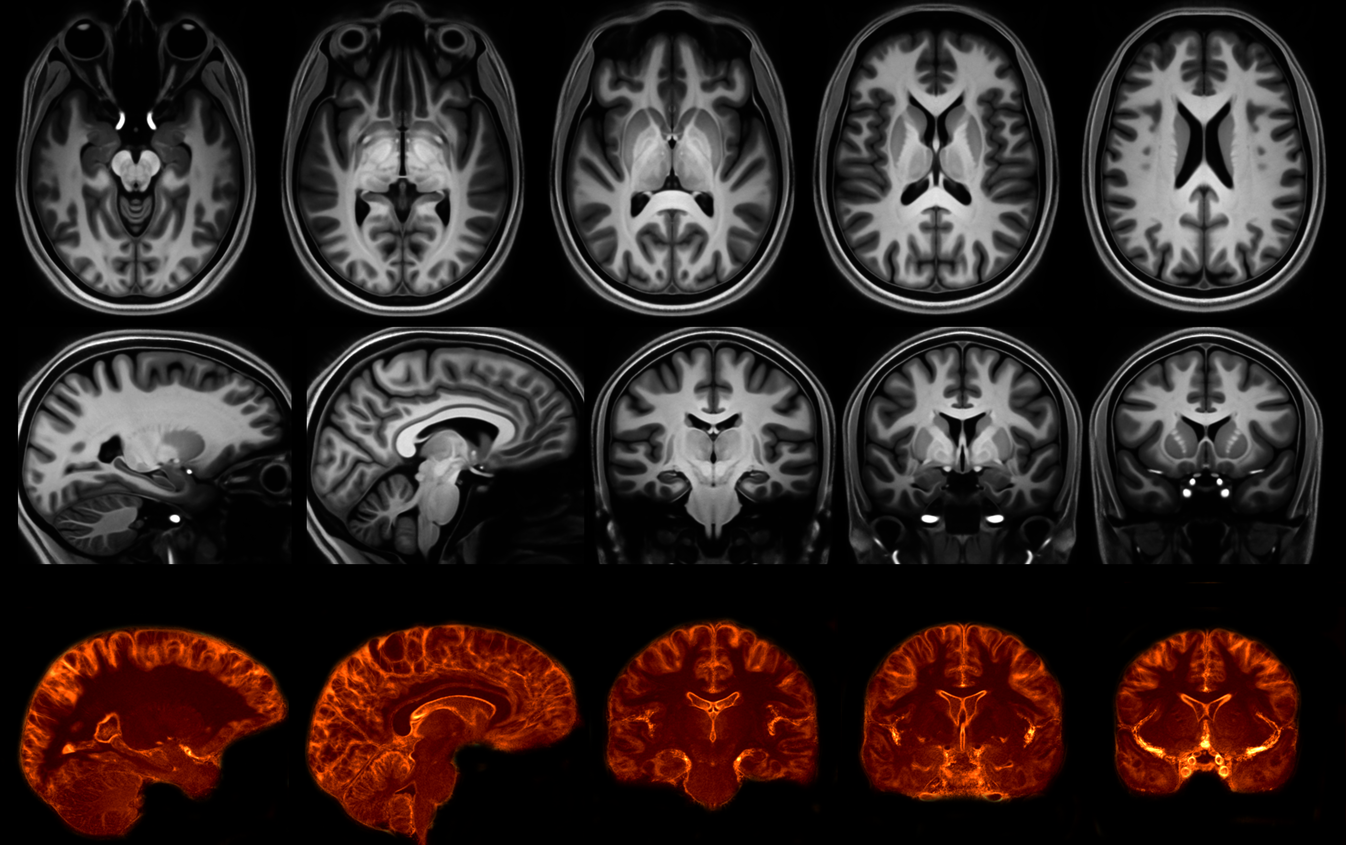

MP2RAGE T1-weighted average 7T model

mp2rageModel_L13_work03-plus-hippocampus-7T-sym-norm-mincanon_v0.8 [  View model online  | Download mnc (1074 MB) | Download nii (1465 MB) ]

Janke AL, O'Brien K, Bollmann S, Kober T, Marstaller L, Barth M. A 7T Human Brain Microstructure Atlas by Minimum Deformation Averaging at 300um. In 24th Annual ISMRM Scientific Meeting and Exhibition, Singapore.

MP2RAGE: 48 (16 female, 31.1±8.6yr) individuals were imaged using a prototype MP2RAGE sequence with a range of resolutions: 0.5mm (18 indiv.), 0.75mm (21), 1.0mm (8) and 1.3mm (1). TR= 4330ms, TI1/TI2=750/2370ms, TE=2.8ms, flip angle=5,6, and GRAPPA = 3. The image matrix was typically 256x300x320 or 420x378x288 but was dependent upon coverage and FOV. The MP2RAGE denoised images [6, 7] were intensity-normalised using a histogram clamping technique.